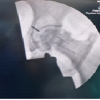

A 52-year-old man presented to the emergency room with an Evans type 2 intertrochanteric hip fracture. Proximal femoral nailing with a proximal femoral nail antirotation II (PFN A2) implant was planned. Under spinal anesthesia, closed reduction was achieved on a fracture table in the supine position. The guide wire was inserted from the tip of the greater trochanter (GT) using a skin incision 7 cm proximal to the GT. An appropriately sized nail was inserted after proximal reaming. A 3 mm guide wire was then used to insert the helical blade from the lateral cortex to the femoral head. However, while inserting the helical blade, it was observed that a broken piece of the guide wire had been pushed into the hip joint and pelvis with the blade still midway in its tract (Fig. 1a). Various options for the retrieval of the broken guide wire were discussed immediately. The helical blade and nail were removed, and the blade tract was manually followed with a size 8 tibia reamer up to the distal tip of the broken guide wire. Under fluoroscopic guidance, a disc forceps was used to retrieve the free end of the broken piece. The fracture was then ultimately fixed with a dynamic hip screw system (Fig. 1b). The post-operative course was uneventful, and the patient recovered well.